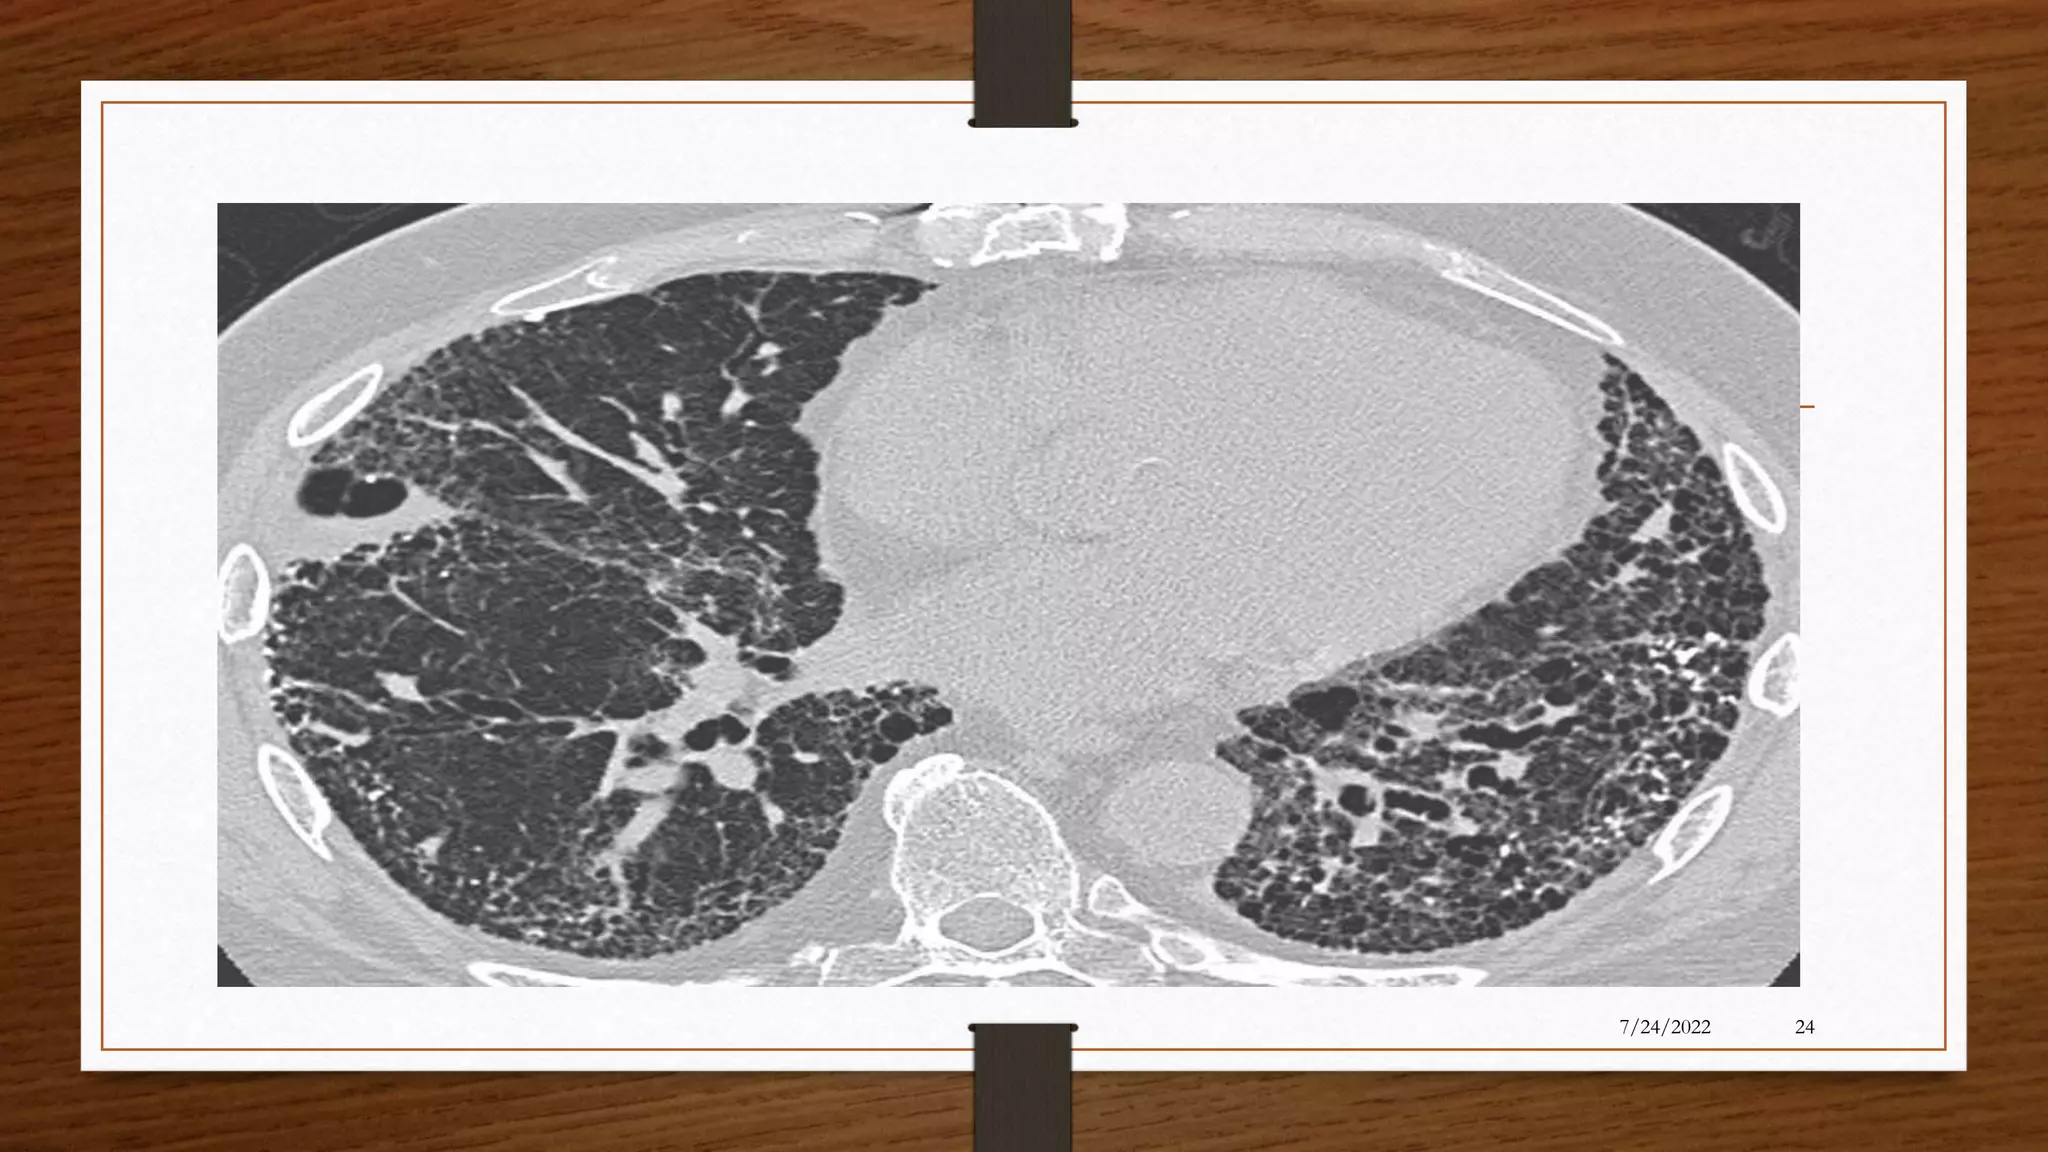

• Chest CT scan: provides further information on disease location, presence

of mediastinal lesions, and the extent of segmental involvement.

• Chest x-ray: increase in size and loss of definition of bronchovascular

markings, crowding of bronchi, and loss of lung volume. Severe case:

honeycombing appearance

• HR CT(High Resolution Computed Tomography) is gold standard for

diagnostic bronchiectasis, it will show either the presence or absence of

bronchial dilation